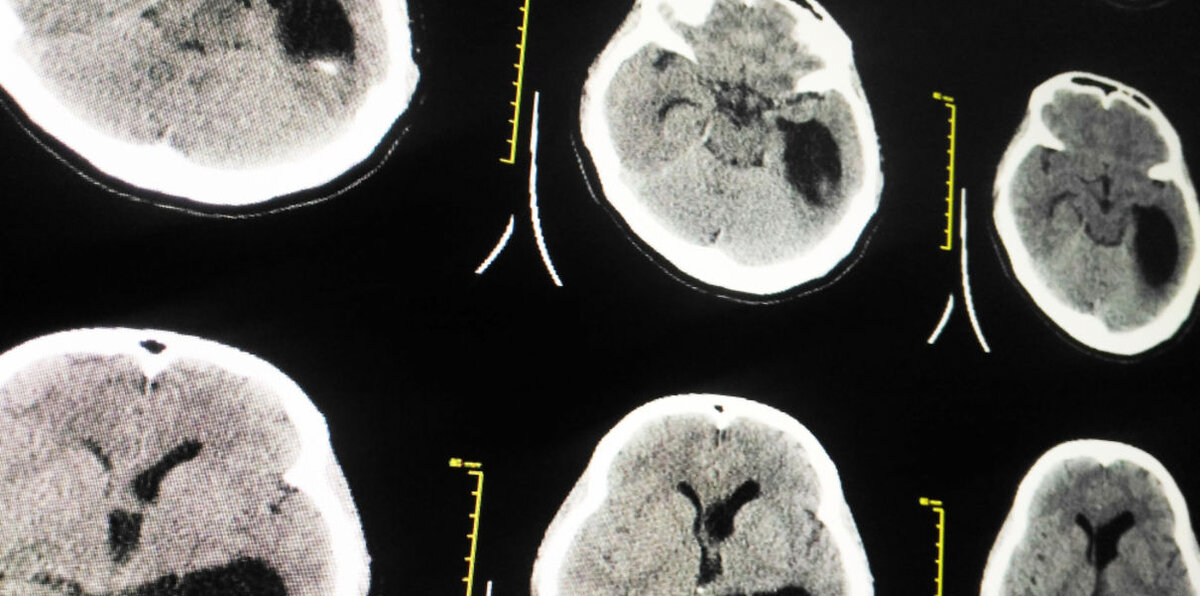

Наш головной мозг состоит из 100 миллиардов нервных клеток (нейронов). Каждая образует от ста до десяти тысяч связей с другими нейронами. Точки контакта между ними (синапсы) могут быть как возбуждающими, так и тормозящими, быть включенными или выключенными. Можете ли себе представить, сколько возможных комбинаций доступны при таком подходе?

Более того, нейроны находятся не в хаотичном порядке, они объединены в сети, каждая из которых выполняет свою определенную функцию. Задумывались ли вы когда-нибудь о том, что бывает при возникновении нарушений в их работе?